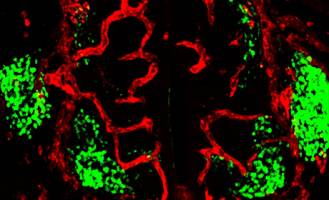

Einen entscheidenden Regulator für die Bildung von Blutgefäßen im sich ausbildenden Rückenmark während der Embryonalphase haben Heidelberger Neurowissenschaftler identifiziert. Sie konnten zeigen, dass spezielle Nervenzellen - sogenannte Motoneuronen - diesen Vorgang kontrollieren. Durchgeführt wurden die Forschungsarbeiten unter der Leitung von Dr. Carmen Ruiz de Almodóvar am Biochemie-Zentrum der Universität Heidelberg.